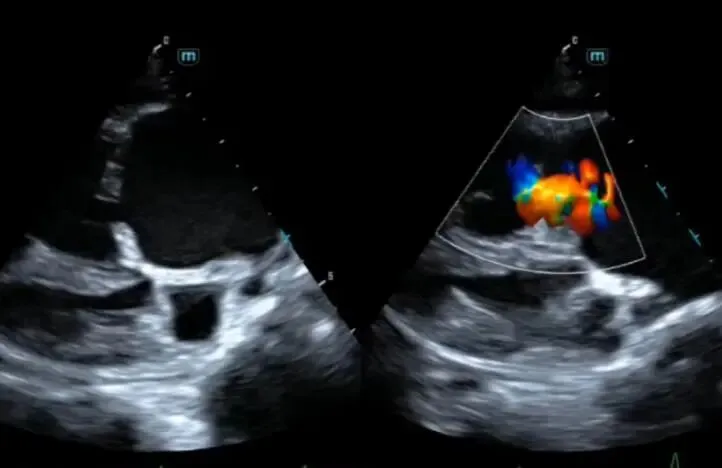

医学上的全称叫心脏超声检查,是一种无创、无痛、动态观察心脏结构与功能的影像技术。它就像一面“照妖镜”,能看清心脏的各个组成部分是否协调运作。……………………………………………………………………….

第三项则是心脏瓣膜结构与功能。瓣膜好比是心脏里的“闸门”,开得不紧就漏水,关得太死又堵塞交通。

彩超可以很清楚地看到二尖瓣、三尖瓣、主动脉瓣、肺动脉瓣这四大“闸门”是否有返流、狭窄、钙化等异常。如果检查提示瓣膜结构清晰、无明显返流或狭窄,那么心脏的“交通系统”就是顺畅的。

很多人看到心脏彩超报告有“轻度返流”字样就慌了,其实这往往是生理性的,如同水龙头滴水一样常见。只要不影响血流方向和量,医生往往并不认为是病变。真正需要警惕的,是“中度以上”且伴有症状的返流。